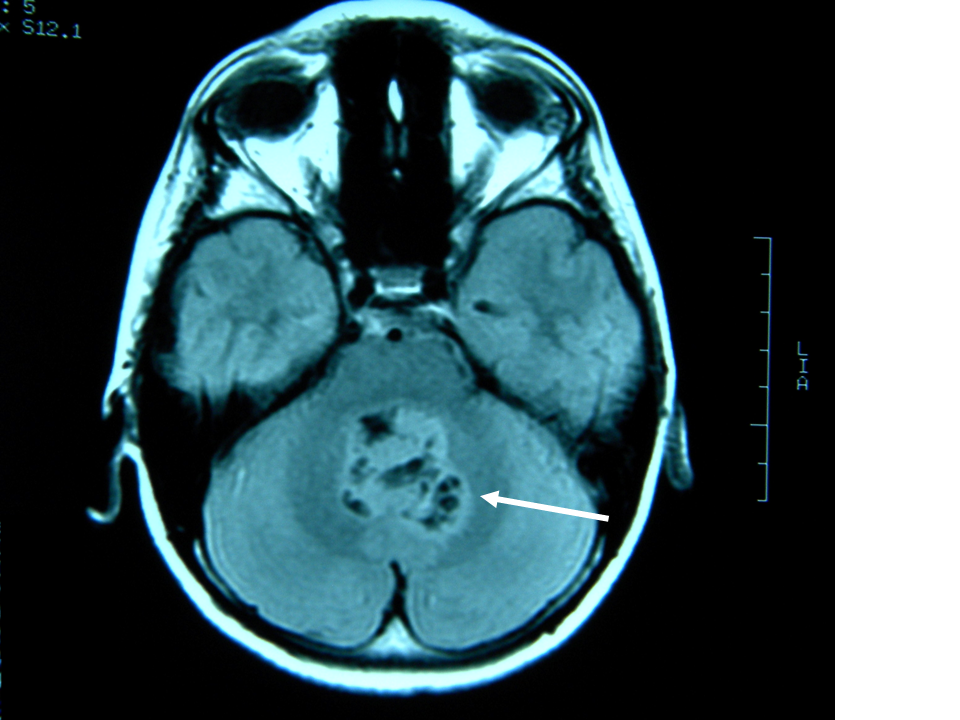

A fine maggio L. viene quindi ricoverato presso il nostro centro per vomito persistente e calo ponderale. L. ha 13 anni e 10 mesi e pesa 39,5 kg (< 10�); la madre riferisce un calo ponderale di circa 13 kg in 4 mesi. Vengono inizialmente formulate alcune ipotesi diagnostiche: RGE, esofagite eosinofila, gastrite Helicobacter pylori-positiva. L. viene sottoposto a una serie di esami di laboratorio e strumentali: le uniche alterazioni riscontrate sono rappresentate da una eosinofilia relativa, da un aumentato livello sierico di IgE e da una positivit� degli skin prick test per pollini di paritaria, acari della polvere e della farina, epitelio di cane e gatto; alla valutazione cardiologica viene rilevata una frequenza cardiaca di 65 bpm. Si decide di eseguire a una nuova EGDS che mostra reperti compatibili con esofagite da reflusso, antrite e reflusso duodenogastrico. Nel sospetto di una ulteriore componente psicogena o neurologica del vomito viene richiesta una valutazione neuropsichiatria infantile che rileva una spiccata deflessione del tono dell�umore necessitante di terapia con valproato, consiglia l�esecuzione di un ulteriore valutazione del fundus oculi e l�esecuzione di RM cerebrale. Il fundus oculi, eseguito nella stessa giornata, non mostra alterazioni patologiche. Alla RM viene evidenziata una neoplasia cerebellare mediana a livello del IV ventricolo (Figura 1 e Figura 2), con iniziale discesa delle tonsille cerebellari nel forame magno e sistema ventricolare sovratentoriale moderatamente dilatato con lievi segni di tensione liquorale; viene eseguita anche una scansione del rachide che evidenzia nodulazioni a livello del sacco durale di L5-S1-S2 da verosimile localizzazione secondaria per diffusione liquorale della neoformazione (Figura 3).

Figura 2. Scansione coronale dell�encefalo in risonanza magnetica: neoplasia cerebellare mediana.